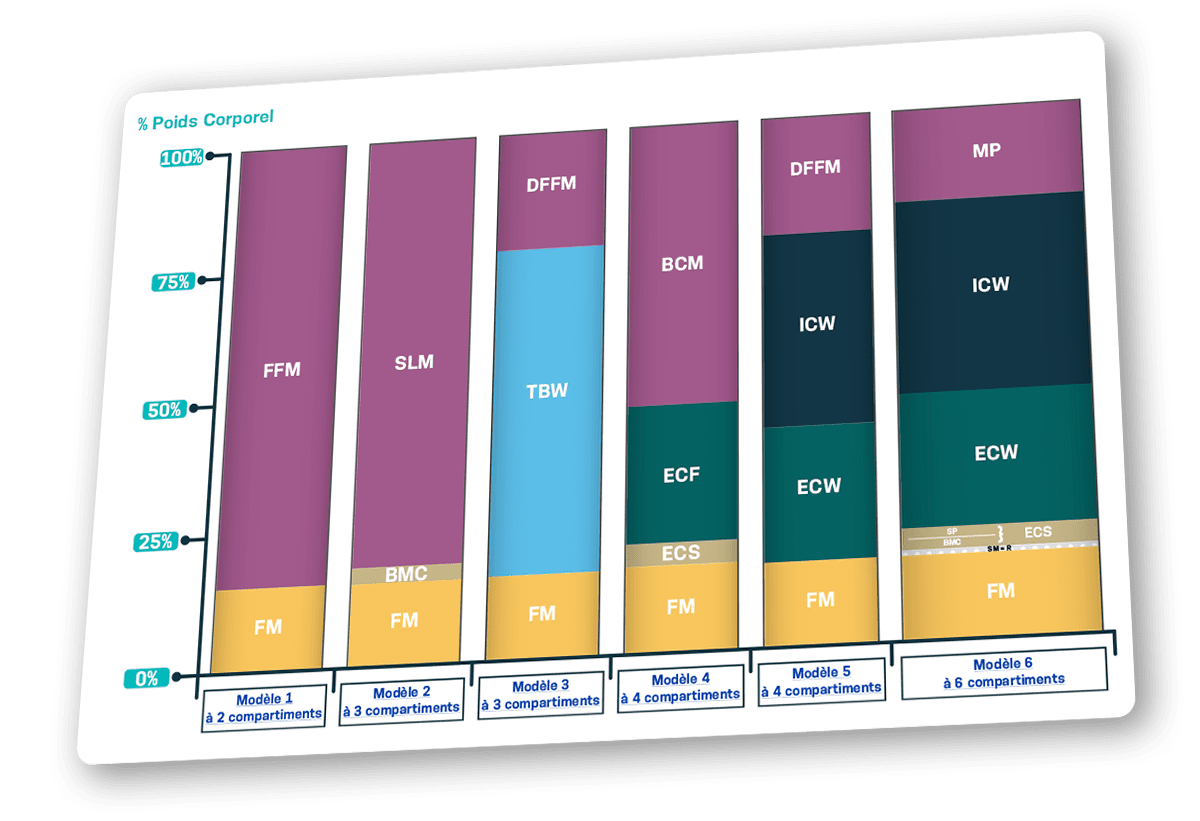

Les compartiments corporels et les modèles d’analyse de la composition corporelle

Il existe 3 modélisations possibles de la composition corporelle

- Biochimique

Mesure directe effectuée sur des cadavres et servant de référence pour les autres techniques

- Anatomique

Mesure indirecte utilisée en imagerie médicale

- Physiologique

Mesure indirecte utilisée en bioimpédancemétrie

La résistance des tissus au passage du courant varie en fonction du type de tissu et de la fréquence utilisée, c’est ce qui permet de déterminer les compartiments corporels.